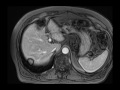

Pseudolipoma of Glisson's Capsule

Multiple MR and CT images demonstrate a fatty mass arising along the capsule of the right hepatic lobe near the dome, compatible with a pseudolipoma of Glissons capsule